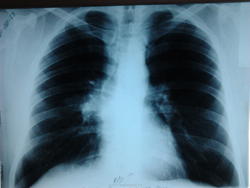

центральный рак правого легкого!?

скорее ТВГЛУ, что возможно в этом возрасте чаще, чем рак.

Может и так...но такой однобокий характер поражения...

[/ Ее я тоже исключала . Но почувствовала неладное в S6-посмотрите внимательно,-в его основании -тень некрупного отграниченного инфильтрата с распадом. На обзорном снимке-в прикорневой зоне -участок инфильтрации, вот и выясняла, что ж это такое. Написала,что процесс "наш", а дальше-дело техники. В результате (была и ФБС )-туберкулома с распадом. И туберкулез сегментарного бронха S6. И туберкулез ВГЛУ.Предвижу вопрос-не ВИЧ, в том-то и дело. Необычно,но бывает.